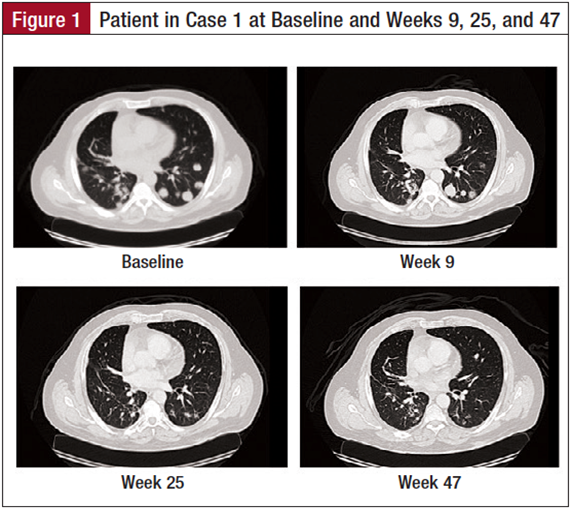

The patient is a 60-year-old man with a 5–pack-year smoking history who quit smoking 31 years prior to presentation (Figure 1). He began complaining of right arm pain in November 2011. A chest computed tomography (CT) scan showed a 4.5-cm lesion in the right upper lobe abutting the pleura. A percutaneous needle biopsy of the lung mass was undertaken, which showed sheets of malignant-appearing cells with glandular features and areas of necrosis. The tumor cells were positive for TTF1, napsin A, cytokeratin (CK) 7, and CD56, and negative for CK20, CK5/6, p63, chromogranin, and synaptophysin consistent with primary adenocarcinoma of the lung. Upon review of his case in a multidisciplinary setting, he was offered chemotherapy with cisplatin and pemetrexed as an initial course of therapy. He had an evaluable response to chemotherapy with evidence of tumor shrinkage, enabling him to be referred for a surgical resection. He underwent a right upper lobectomy. Pathology was consistent with high-grade carcinoma with a prominent neuroendocrine pattern. The tumor was 4.0 cm in greatest dimension and approached the perivascular soft tissue. Mediastinal lymph nodes were negative for any evidence of malignancy. He did not receive chemotherapy in the adjuvant setting.

Six months following the patient’s surgery, surveillance CT scans showed evidence of new lesions in the left lung. Percutaneous biopsy of one of the pulmonary lesions was consistent with recurrent TTF1-positive, CK 7-positive, napsin A-negative, and thyroglobulin-negative cells consistent with adenocarcinoma of the lung. He was negative for EGFR and ALK mutations. Because of his prior experience with chemotherapy, the patient was reluctant to undergo further chemotherapy for his now stage IV disease. He opted to participate in a dendritic cell vaccine study to which he initially had a mixed response followed by progression 3 months after enrollment. Upon progression, he was offered treatment with systemic chemotherapy. However, the patient requested to pursue various trial options, ultimately presenting to our clinic for consideration of an immunotherapy trial with a checkpoint inhibitor.

In July 2013, the patient was evaluated for an anti–PD-1 antibody immunotherapy trial and underwent a biopsy of a pulmonary lesion, which was tested for PD-L1 protein expression. The disease was found to express PD-L1. His CT scans prior to enrollment indicated the presence of multiple bilateral pulmonary nodules, the largest of which was 2.5 cm. There was no evidence of pleural effusion, but the patient had a small pericardial effusion. His first scan 9 weeks after initiating therapy indicated stable disease; all subsequent scans have indicated significant tumor shrinkage. The patient has tolerated therapy well with no significant side effects, except for complaint of bilateral buccal mucosal swelling and sensitivity. He has also developed oral ulcers that have been managed well with oral lidocaine and a steroid solution. He has had no other side effects, and continues to do well on the trial 1 year after enrollment.